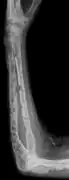

X-ray of the forearm, with lytic lesions

The diagnostic examination of a person with suspected multiple myeloma typically includes a skeletal survey. This is a series of X-rays of the skull, axial skeleton, and proximal long bones. Myeloma activity sometimes appears as "lytic lesions" (with local disappearance of normal bone due to resorption) or as "punched-out lesions" on the skull X-ray ("raindrop skull"). Lesions may also be sclerotic, which is seen as radiodense.[70] Overall, the radiodensity of myeloma is between −30 and 120 Hounsfield units (HU).[71] Magnetic resonance imaging is more sensitive than simple X-rays in the detection of lytic lesions, and may supersede a skeletal survey, especially when vertebral disease is suspected. Occasionally, a CT scan is performed to measure the size of soft-tissue plasmacytomas. Nuclear Medicine Bone scans are typically not of any additional value in the workup of people with myeloma (no new bone formation; lytic lesions not well visualized on nuclear bone scan).